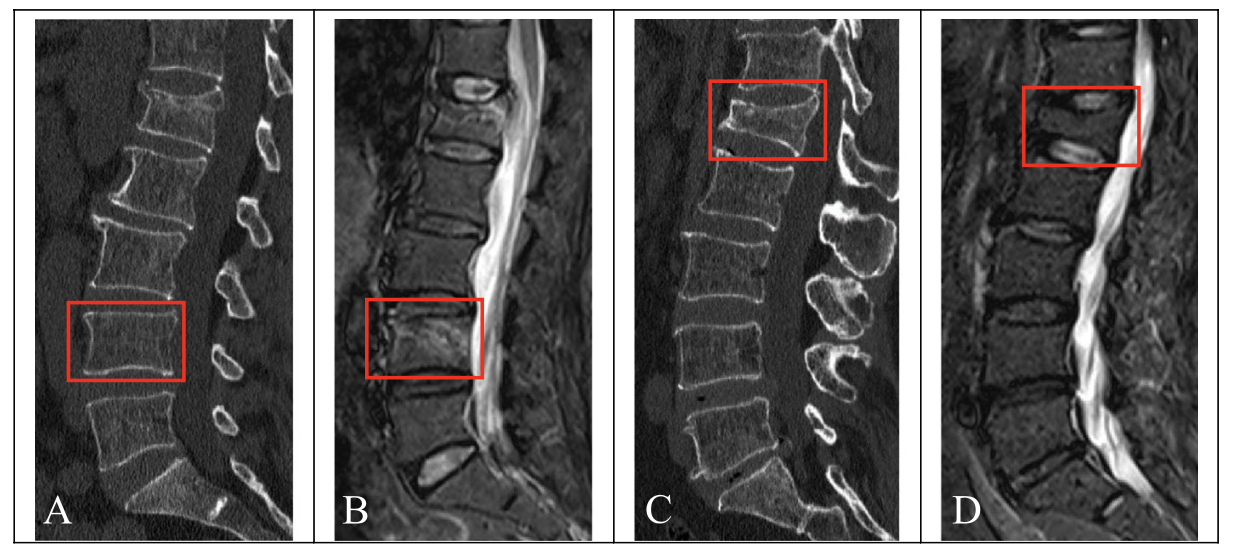

新鮮な骨折(骨折してから概ね2-3カ月以内)では, MRIで椎体が白く写りますが(上図B), 旧い骨折(骨折してから概ね4カ月以上経過)では, 椎体が潰れていても(上図C), MRIでは椎体が白く写らずに, 骨折のない椎体と同じような色合いに写るようになります(上図D).

撮像されたX線写真を見たところ, 胸椎と腰椎が3箇所で潰れて骨折していましたが, MRIでは骨折の所見がなく, 数ヶ月以上前の旧い骨折であると診断しました. 骨盤の骨にも異常はなかったので, 打撲傷と診断して, 鎮痛薬を処方して, 帰宅していただきました.